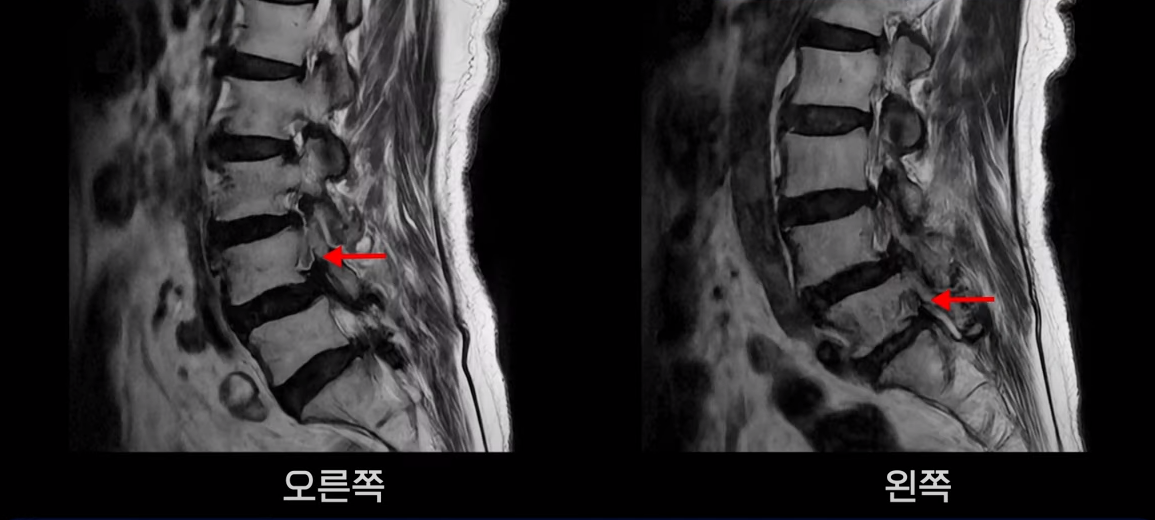

먼저 이분 MRI를 보면서 자세히 설명 드리겠습니다. 보시다시피 허리 여러 마디가 안 좋습니다.

특히 4번 5번에는 심한 중심성 협착이 있어 척추관이 매우 좁아져 있습니다.

5번 1번도 척추관이 좁아져 있고 특히 좌우 신경이 빠져나가는 추간공이 좁아져 있는데 5번 1번 왼쪽 추간공은 많이 좁아져서 신경이 눌리고 있습니다.